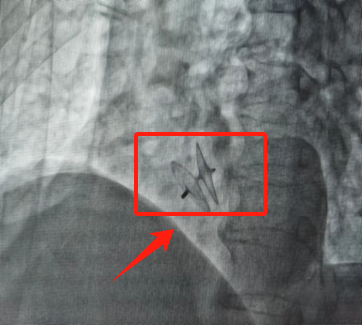

薛城区人民医院完成首例卵圆孔未闭介入封堵术

近日,薛城区人民医院心血管介入团队成功为一名卵圆孔未闭患者实施封堵术,为该院首例。

患者老年女性,于6月30日因“反复头痛、头晕”就诊薛城区人民医院神经内科,经心脏超声及右心声学造影诊断为卵圆孔未闭。经心血管内科会诊,考虑患者反复头痛与卵圆孔未闭相关。与家属充分沟通病情后,决定实施卵圆孔未闭介入封堵微创治疗。手术于7月3日进行,仅在患者股静脉穿刺处给予局部浸润麻醉,在完全清醒状态下,经股静脉穿刺处置入导丝,导管从股静脉到达下腔静脉,然后到达右心房,将封堵器送到卵圆孔未闭处进行封堵。手术40分钟,顺利完成。术后患者头痛症状明显缓解,次日出院。